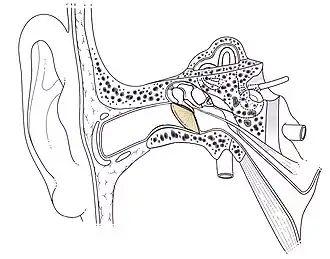

En anatomie, le tympan est une membrane fibreuse séparant l'oreille externe et l'oreille moyenne. Le tympan est chargé de récolter les vibrations dues aux sons arrivant par le conduit auditif externe, et de les transmettre à la chaîne ossiculaire.

Le tympan a une forme arrondie légèrement plus étroite dans le sens antéropostérieur (sa hauteur est en moyenne de 10 mm sa largeur de 8 mm). Il n'est pas dans un plan sagittal mais regarde en avant en bas et en dehors. De ce fait, il a une surface plus grande que la section du conduit auditif externe, soit environ 60 mm2. Le tympan n'est pas une membrane plane, mais a une forme de cône, dont le sommet, correspondant à l'ombilic du marteau, est déprimé vers l'intérieur de 2 mm par rapport aux bords.

Insertion

Le tympan s’insère dans le sillon tympanique (sulcus) par l’intermédiaire d’un bourrelet fibreux annulaire dit de Gerlach. Cet anneau, au niveau de l’échancrure de Rivinus, s’insère sur la courte apophyse du marteau en donnant les ligaments tympano-malléolaire antérieur et postérieur.

Le tympan peut être visualisé grâce à un examen otoscopique. Le schéma suivant révèle les différentes parties du tympan :

Tympan droit normal. Schéma simplifié du tympan droit.

- Légende du Schéma simplifié du tympan droit

- Incisure de Rivinus

- Pars flaccida

- Manche du marteau (aussi appelé longue apophyse du marteau)

- Pars tensa (membrane épidermique fibreuse)

- Triangle lumineux de Politzer

- Courte apophyse du marteau

- Bourrelet fibro-cartilagineux annulaire de Gerlache

- Ligaments tympano-malléolaires

- Ombilic

Structure

À partir des ligaments tympano-malléolaires on décrit deux parties :

- la pars tensa : située au-dessous des ligaments, elle représente la majeure partie du tympan. Cette portion est la plus rigide. Elle est, de l’extérieur vers l’intérieur, constituée de trois couches :

- La couche épithéliale qui est la continuité de l'épithélium pavimenteux stratifié kératinisé recouvrant l'oreille externe,

- La couche fibreuse, la lamina propria, contenant en grande partie des fibres de collagène très organisées, dans une grande quantité de substance fondamentale. Cette organisation permet au tympan d'avoir ses caractéristiques de plasticité et d'élasticité qui permettent aux sons de le faire entrer en vibration,

- La couche muqueuse : la plus interne est une muqueuse respiratoire de type épithélium cubique, qui recouvre toute l'oreille moyenne ;

- la pars flaccida ou membrane de Schrapnell, au-dessus des ligaments, est de très petite taille mais dépourvue de la couche intermédiaire fibreuse, ce qui en fait un point de fragilité électif de l’édifice.